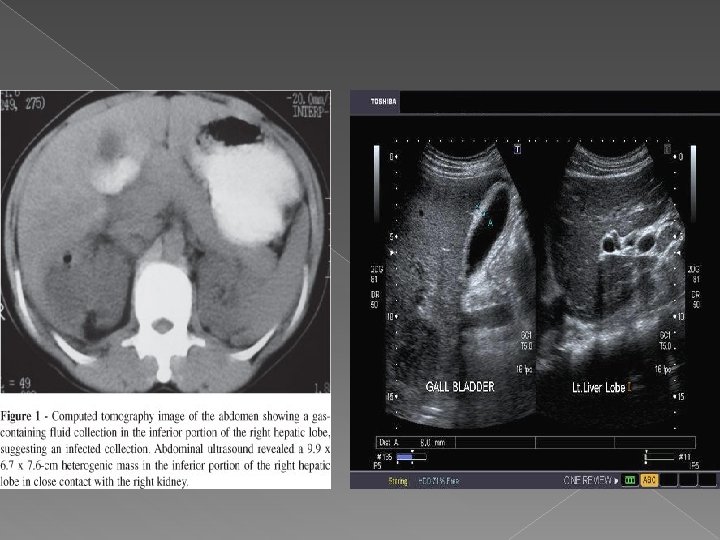

Abces hepatic

Computer tomografia Tehnica: -sectiuni contigui de 8 -10 mm, 5 mm pentru hil si cai biliare -nativ +contrast: cu rol in diferentierea leziunilor de parenchimul normal q Leziunile focale • Sunt de regula spontan hipodense • Incarcare mai mica decat a parenchimului hepatic Exemple: v Tumori hepatice-primitive sau secundare v Chiste; v Abcese; v Hematoame; v Steatoza.